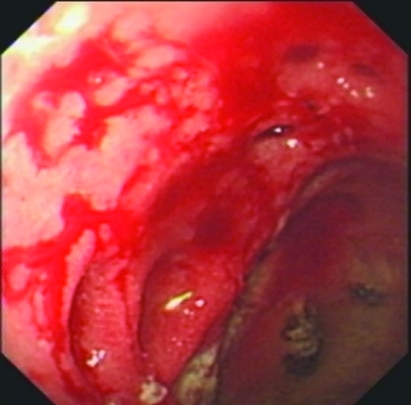

Endoscopic view of multiple gastric stromal tumors after suctioning of hemorrhagic products (Courtesy Dr. V. Penopoulos)